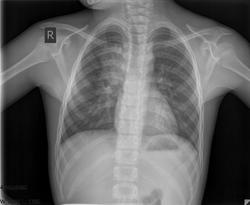

рентгенконтроль

ogk_3.jpgogk_4.jpg

Ну и все прекрасно, хорошо полечили пневмонию.

Значит, надо писать норму?

Хорошую положительную динамику, а вам, Валентин Львович, что-то не нравится? Кстати, есть новости о ребенке с расширенным средостением?